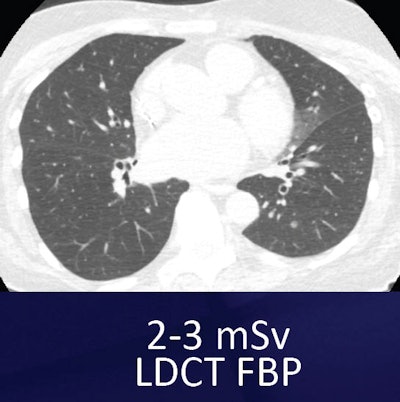

For example, one commercially available MBIR protocol (Veo, GE Healthcare) has shown an impressive ability to reduce noise and improve contrast and spatial resolution, she said. The technique, cleared by the U.S. Food and Drug Administration (FDA) in 2011, uses advanced modeling of system statistics and optics to increase spatial and contrast resolution while permitting vastly lower radiation doses -- as low as 0.2 mSv -- in the lungs.

Compared with low-dose and ultralow-dose filtered back projection (FBP), ultralow-dose MBIR significantly reduced objective noise (p < 0.01). Still, compared with low-dose FBP, ultralow-dose MBIR and ultralow-dose FBP showed reduced image sharpness (p < 0.001).